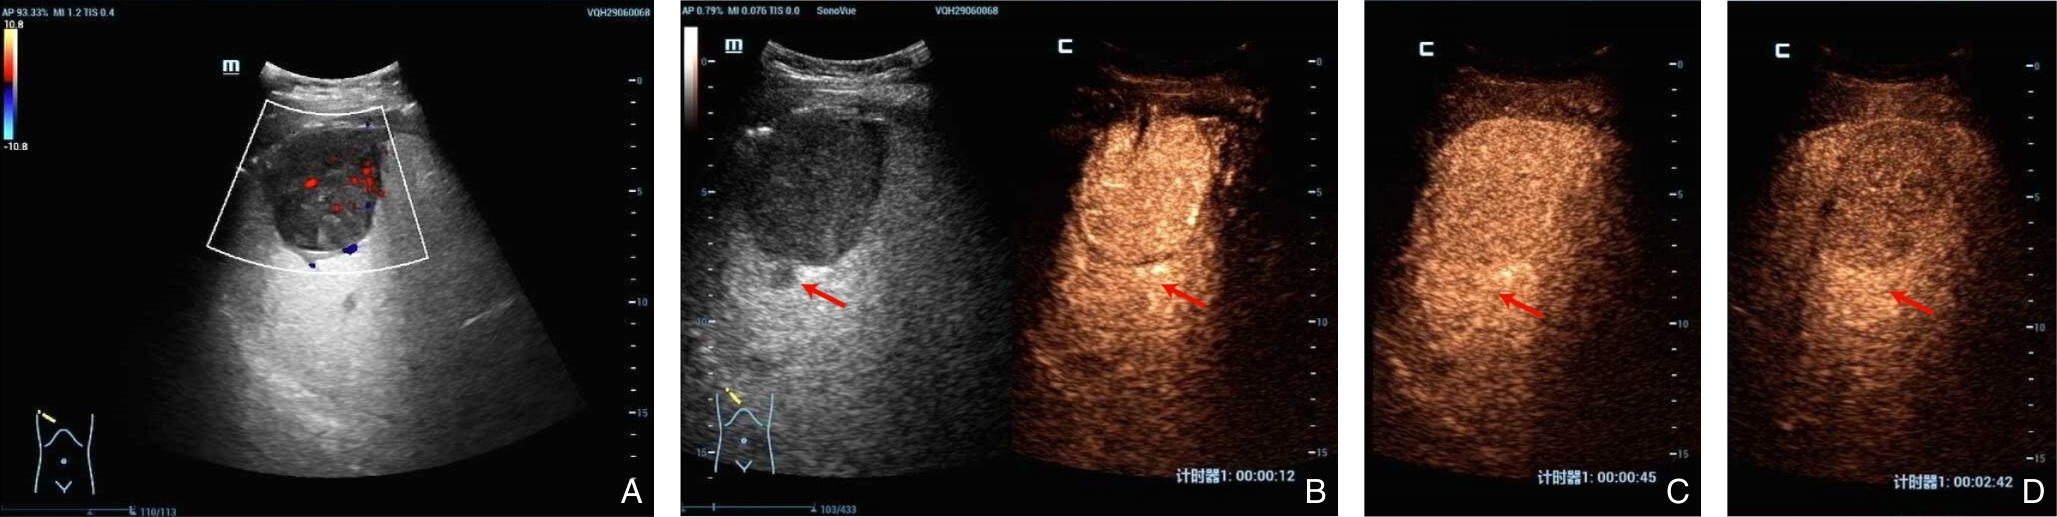

2026, 35(1):141-148. DOI: 10.7659/j.issn.1005-6947.250622

Abstract (79) HTML (119) PDF 1.24 M (183) Comment (0) Favorites

Abstract:Background and Aims Hepatocellular carcinoma (HCC) presenting initially with bone metastasis is uncommon, and metastasis to the appendicular skeleton is particularly rare. These cases often lack typical liver disease history, elevated alpha-fetoprotein (AFP), or characteristic imaging findings, leading to frequent misdiagnosis or delayed diagnosis. This study reports a rare case of occult HCC presenting with humeral metastasis and reviews the literature to improve clinical recognition and management.Methods The clinical data of a 42-year-old male patient presenting with humeral metastasis as the initial manifestation admitted in August 2025 were retrospectively analyzed, including laboratory tests, multimodal imaging findings, histopathological and immunohistochemical results, treatment, and follow-up outcomes. Relevant literature was also reviewed.Results The patient presented with left shoulder pain. Imaging revealed osteolytic destruction of the left humerus. PET/CT incidentally detected multiple hepatic lesions without significant FDG uptake. Contrast-enhanced ultrasound demonstrated atypical enhancement patterns, initially suggesting a perivascular epithelioid cell tumor. Histopathological and immunohistochemical examination of biopsy specimens from both the humeral and hepatic lesions confirmed moderately differentiated hepatocellular carcinoma with humeral metastasis (CNLC stage IIIb). The patient received systemic therapy with sintilimab plus bevacizumab, followed by transcatheter arterial chemoembolization. After 6 months of follow-up, the intrahepatic lesions had decreased in size, the bone metastasis remained stable, and pain symptoms were significantly relieved.Conclusion HCC presenting with humeral metastasis as the initial manifestation is extremely rare and may lack typical imaging and serological features. Clinicians should consider HCC in patients with unexplained bone metastasis even in the absence of liver disease history or elevated AFP. Multimodal imaging and pathological biopsy are essential for accurate diagnosis and appropriate management.